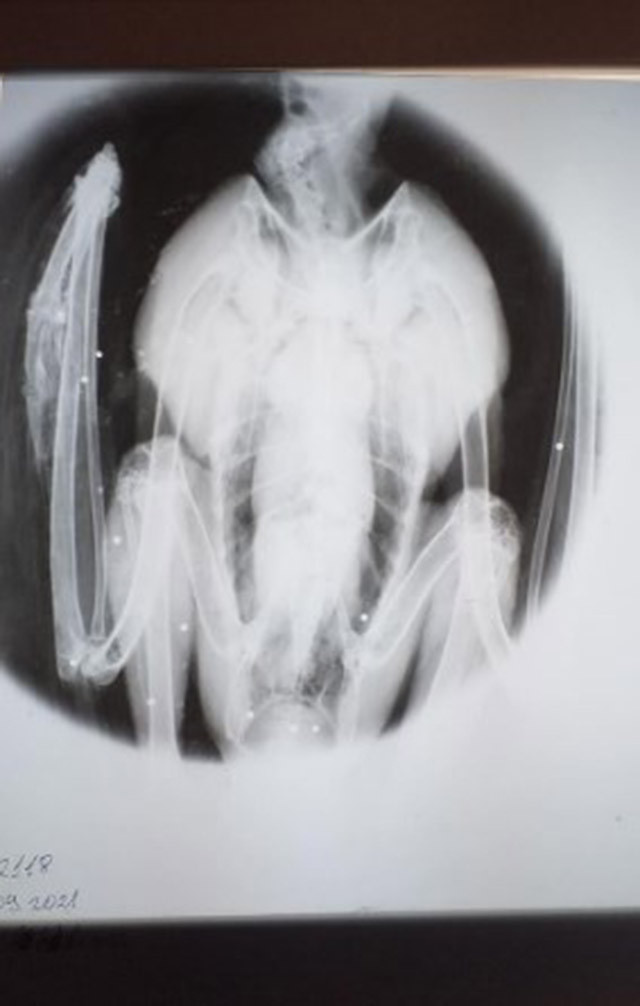

Царски орел в тежко положение е открит в безпомощно положение в равнища покрай град Ямбол. Екип на Българското сдружение за отбрана на птиците (БДЗП) съумява да открие птицата, с помощта на поставения й GPS/GSM предавател. Птицата е настанена в Спасителния център за диви животни на " Зелени Балкани ", а прегледът открива, че орелът е прострелян с ловно оръжие, със счупено ляво крило. Снимка с рентген открива 16 сачми в тялото му. Орелът несъмнено е жертва на бракониери, уверени са от Българско дружество за защита на птиците.

Сачми са открити из цялото тяло, в това число в региона на крайните прешлени на гръбнака, където могат до доведат до трайно обездвижване на орела. Според ветеринарните експерти на Спасителния център, където птицата се лекува, положението й продължава да бъде сериозно. Царският орел е млада птица, маркирана с GPS/GSM предавател това лято в гнездо в региона на град Елхово. Предавателите дават опция да се получава информация в действително време за точните географски координати на местоположението на птиците и да се следи тяхното положение. Данните от сателитната и GPS/GSM телеметрия разкриват значима информация за типа, в това число и за заканите, които заплашват популацията му. Конкретният случай е образец за една от най-сериозните закани - противозаконният лов. Сигнал за случая е подаден до всички виновни институции, в това число и до прокуратурата, от където от Българско дружество за защита на птиците се надяват бързо да образуват досъдебно произвеждане. Царският орел е международно заплашен тип и неговото гонене попада под наредбите на Наказателния кодекс, който планува наказване отнемане от независимост до 5 години и санкция от 5 000 до 20 000 лв..